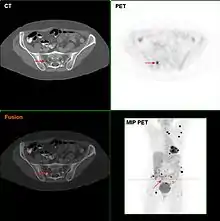

Metastatic melanomas can be detected by X-rays, CT scans, MRIs, PET and PET/CTs, ultrasound, LDH testing and photoacoustic detection.[86] However, there is lack of evidence in the accuracy of staging of people with melanoma with various imaging methods.[87]

It is common for patients diagnosed with melanoma to have chest X-rays and an LDH test, and in some cases CT, MRI, PET, and/or PET/CT scans. Although controversial, sentinel lymph node biopsies and examination of the lymph nodes are also performed in patients to assess spread to the lymph nodes. A diagnosis of melanoma is supported by the presence of the S-100 protein marker.